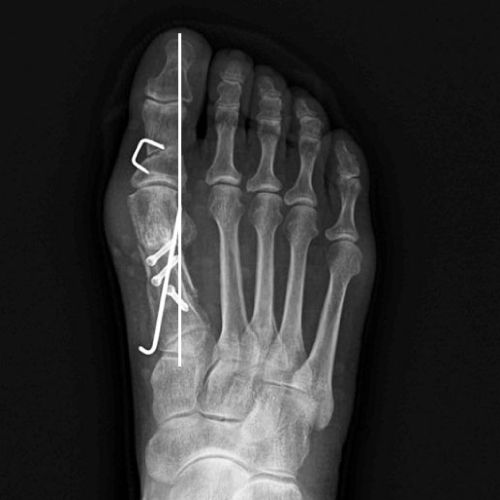

무지외반증 수술 전

2020.12.10

무지외반증 수술 후

2021.01.18

ㆍ환자 동의를 받은 자료이며, 이미지 사진은 실물과 다를 수 있습니다.

수술은 돌출부의 뼈를 자르고 변형이 생긴 뼈의 각도를 교정하는 절골술이 시행됩니다.

기울어진 관절만이 아닌 주변의 인대, 근육, 관절낭까지 정렬하여 교정하기 때문에

발가락뼈의 교정 효과와 함께 망가진 기능 또한 회복되게 됩니다.